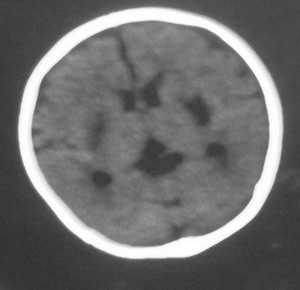

以下是引用dyqct在2008-7-30 17:05:00的发言:[br]考虑:1、胼胝体发育不全;[br] 2、肝豆状核变性(双侧豆状核对称性低密度)。